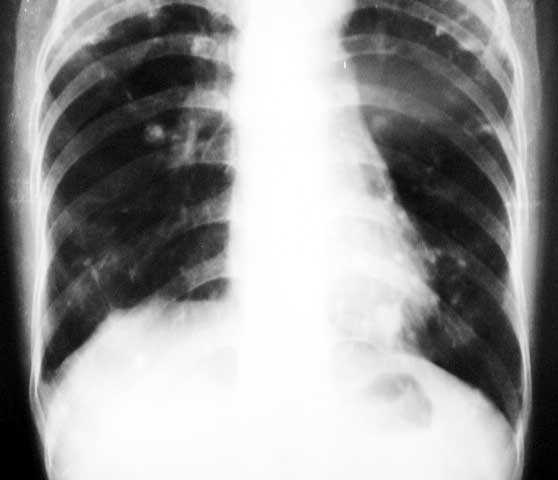

标题: X0226:[原创]两肺结节状高密度

f/63y,胸痛数天,曾患结核性胸膜炎。

1、双上中继发性肺结核,右侧胸膜粘连;

双上肺结节条索。点仗钙化。透光度增强,诊断肺结核,肺气肿

两肺钙化灶,两上胸膜增厚、粘连

意见:1陈旧性肺结核;2右侧胸膜粘连;3两中下肺气肿。

双肺陈旧性结核,双上胸膜粘连